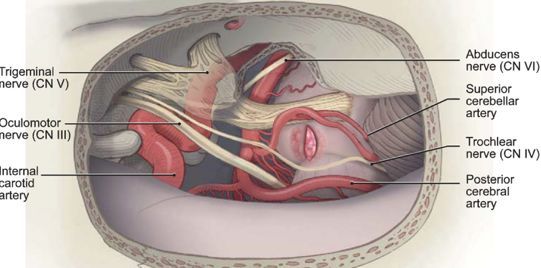

手术方式:颞下经天幕入路

2 脑干出血部位位于基底部和被盖部之间,而后影响到其他脑干分区,手术尽量在脑干安全区进入,以免加重神经功能的损伤。

STEP 01:在脑干表面安全区域附近探寻血肿位置

STEP 02:发现血肿,放出血水减压

STEP 03:清除中脑内脑干血肿

STEP 04:清除桥脑内血肿

本例病人,出血位于脑干基底部和被盖之间,逐渐向其他分区蔓延,选择侧方安全区入路,既不损伤脑干基底部的长传导束,又不损伤被盖部的生命中枢,术后取得了较好的效果。